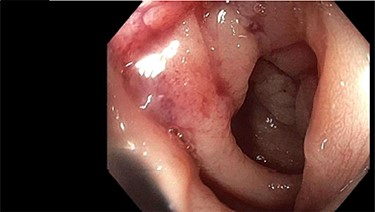

A 62-year-old, previously well, male presented to the emergency department with a 2-day history of colicky lower abdominal pain, distension and obstipation. Relevant background included non-insulin-dependent type two diabetes, coronary artery disease and chronic obstructive pulmonary disease. He was noted to have a sigmoid stricture during an outpatient colonoscopy 3 months prior (for polyp surveillance). Although not completely obstructed, the colonoscope could not traverse this stenosis (Fig. 1). The patient was awaiting outpatient computed tomography (CT) colonography to further evaluate this lesion when he presented to the emergency department with obstructive symptoms.